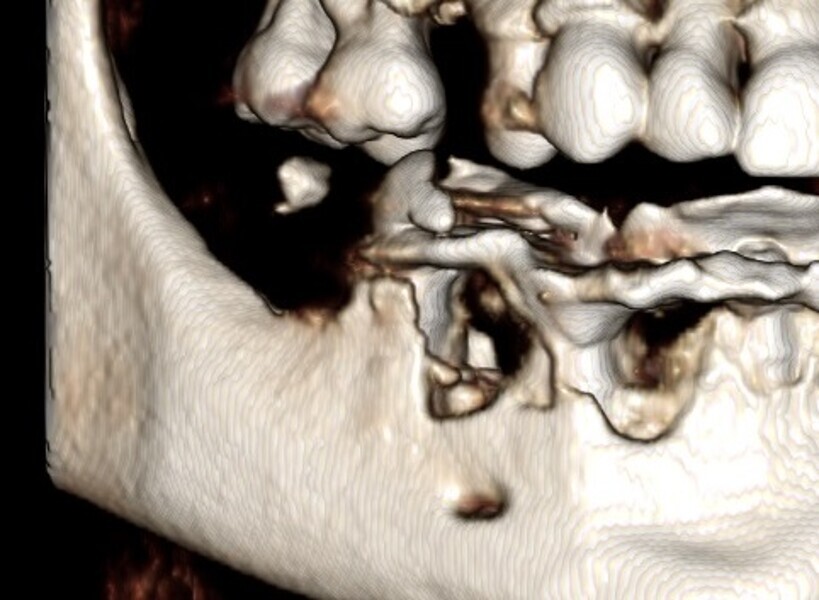

Natychmiastowa implantacja i zaopatrzenie protetyczne pacjentów z zaawansowaną chorobą przyzębia